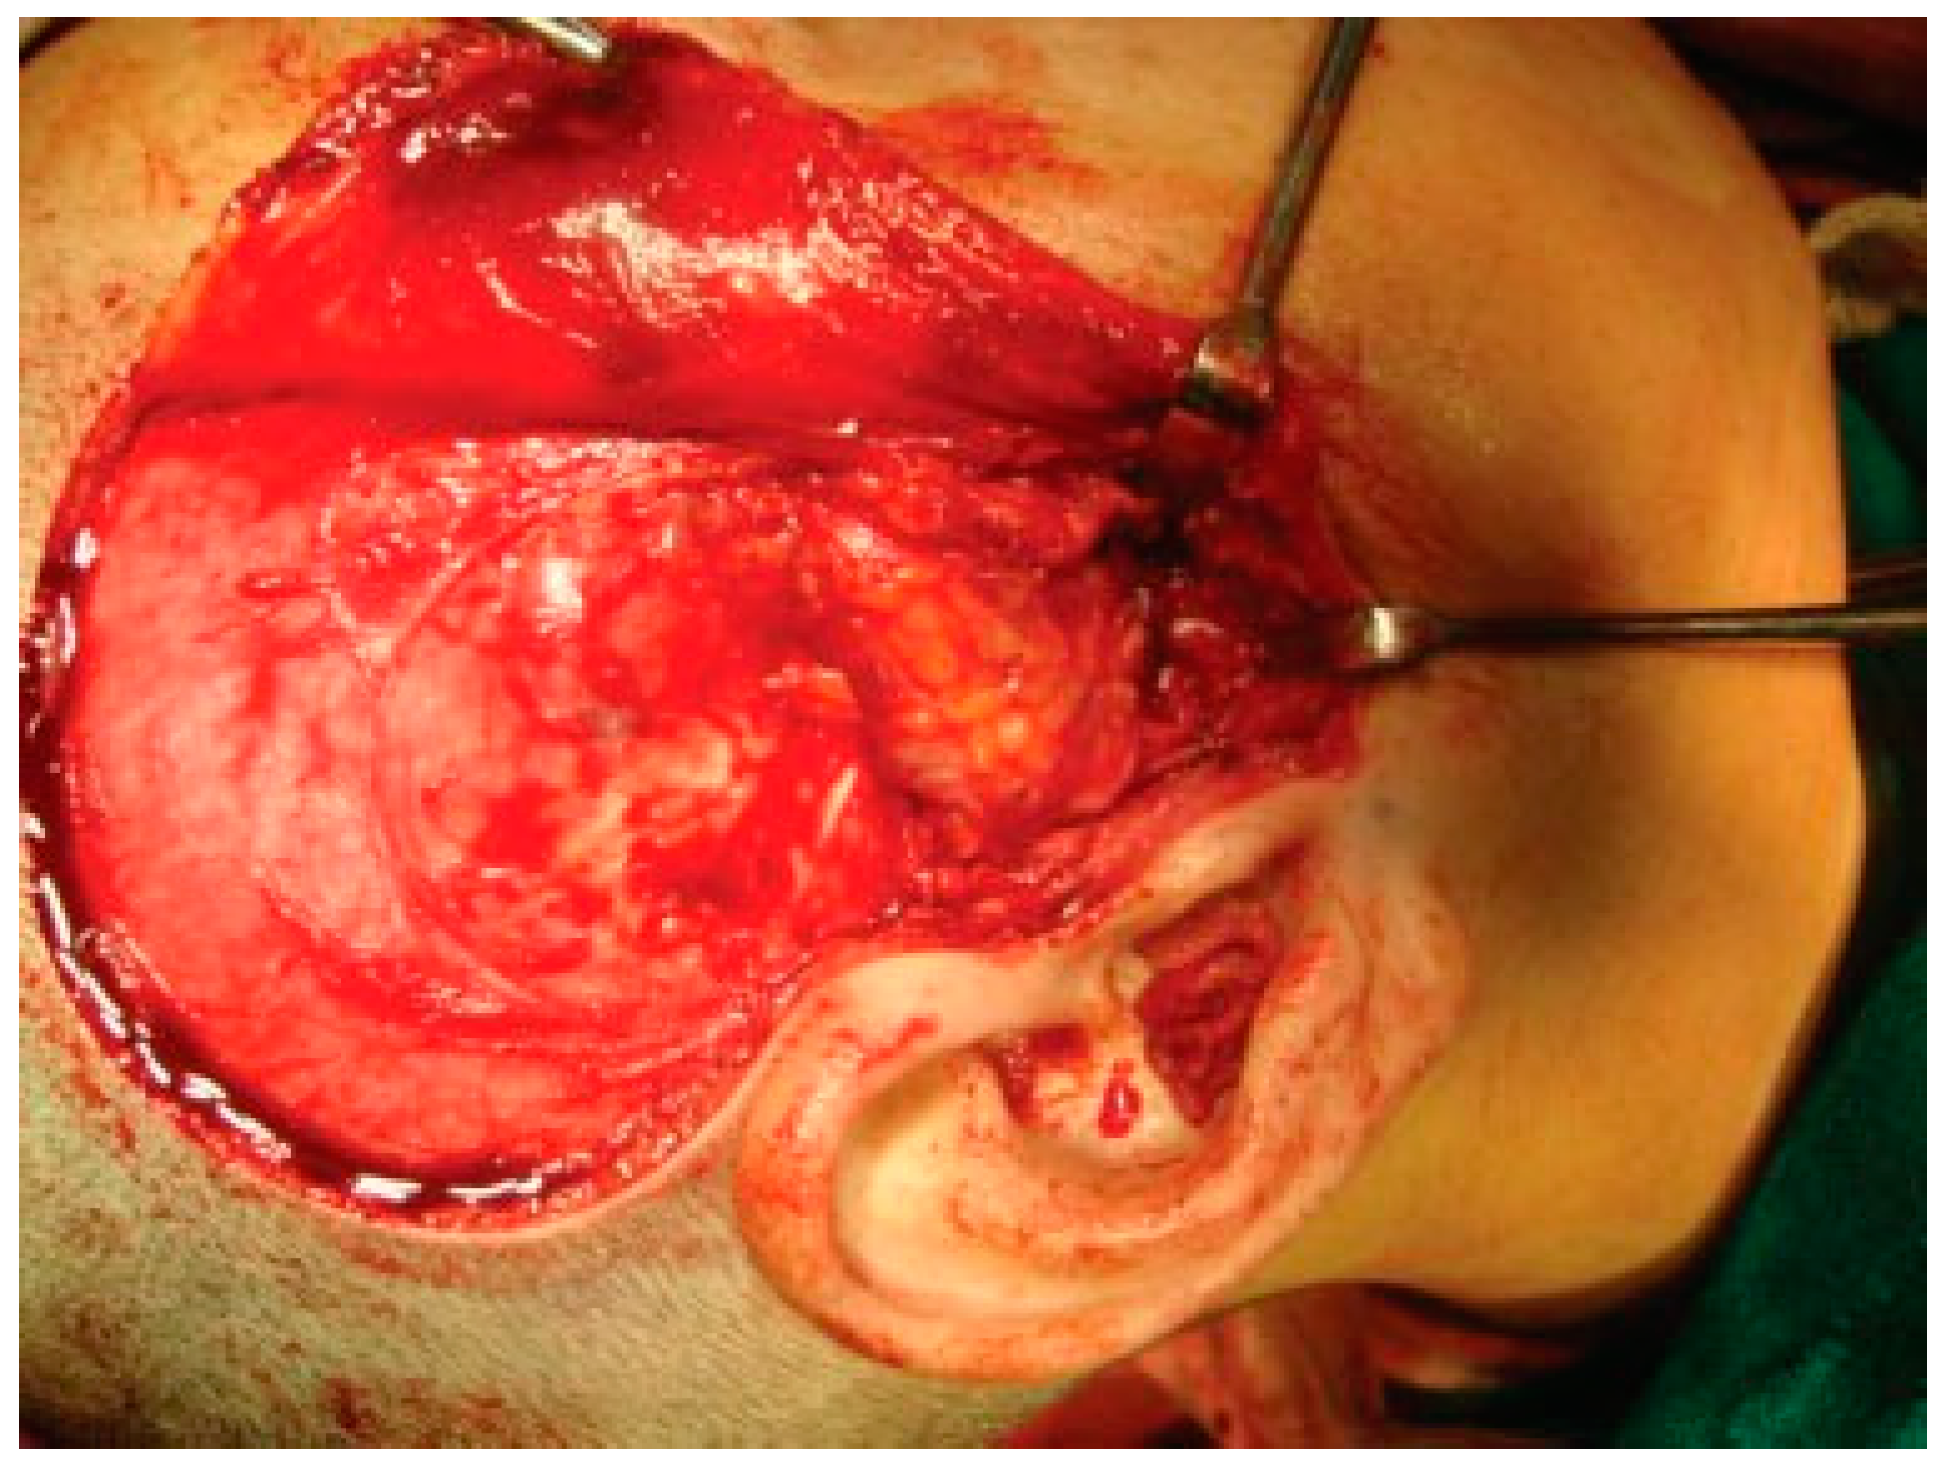

Figure 7. Temporalis muscle flap.

Figure 8. Temporalis muscle interpositioning.

Temporalis muscle was used in seven patients and temporalis fascia was used in two patients. In our series, using temporalis fascia as an interpositional material in the postoperative MIMO was 37 mm. Temporalis fascia has the disadvantage of being thinner, taut, and nonelastic. Long-term follow-up showed premature contact of teeth on the operated side in both the patients and the ramal height was not maintained. When the temporalis muscle was used as interpositional material, we based our flap on one of the branches of deep temporal arteries to maintain its vascularity and the flap was turned over the zygomatic arch and placed into the glenoid fossa. Temporalis muscle provided us with more bulk to obliterate the joint space and was sandwiched between the chondral end of the CCG and temporal bone. After appropriate positioning has been established, the muscle is sutured in both the anterior and posterior directions. Moreover, there is no hematoma formation and hence had better long-term stability. In patients where temporalis muscle was used, the MIMO was 41 mm and ramal height was maintained in all the cases (Figure 7 and Figure 8). The ramal height was preserved in most of our cases possibly due to unilateral ankylosis with compensation by the contralateral mandibular unit. Management of ankylosis in children can be very challenging and our aim was to correct retrognathia in bilateral cases and reduce the possibility of further asymmetry in unilateral cases. Growth center transplantation using CCGs was done in seven growing children in the 6- to 13-year age group. The uses of this biologically compatible autograft in reconstruction are benefits of growth potential and ability to remodel into a neocondyle with time. Unpredictable growth pattern of the CCG, midline shift, and donor site morbidity are some of the disadvantages of this technique. Overgrowth of the graft has been attributed to the use of a large cartilaginous cap; hence, only 1 to 2 mm cartilaginous cap must be used to avoid such complications [13,14,15]. We assessed the same using panoramic radiographs during follow-ups. The CCGs showed excellent mandibular growth along with complete integration of graft into the recipient site over the passage of time in all seven cases. The CCG was harvested from the sixth rib (contralateral side) using submammary incision and was secured using three 2-mm titanium screws at the recipient site. Due to the close proximity of the chondral cartilage to the base of skull, we routinely interposed temporalis muscle in these patients. The muscle pedicle acted as an artificial disc as well as a barrier between the base of skull and chondral cartilage (Figure 9). Early and vigorous mobilization is important to prevent postoperative adhesions and reankylosis [16]. The postoperative MIMO in seven patients was 41.5 mm. Asymmetry in the form of deviation of chin was found in one patient during long-term follow-up, where CCG overgrowth led to the deviation of the chin to the contralateral side.